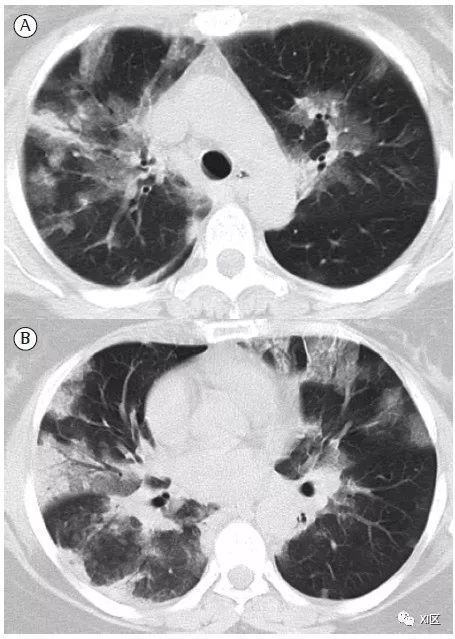

图14 一位22岁女性感染前1个月因急性淋巴细胞白血病接受单倍体相合骨髓移植治疗,有发热,诊断为 HPIV病毒性肺炎。

在主支气管水平(上)和叶间区水平(中上)的初始轴位胸部CT图像显示沿支气管血管束和轻度支气管壁增厚(箭头)的多灶性不明确结节性GGO病变(箭)。中性粒细胞减少持续存在。(中下,下)随访10天后获得的轴位胸部CT图像显示病变的范围和强度增加,并沿支气管血管束增加不规则的实变结节(箭)。尽管进行了重症监护,该患者仍然死亡。